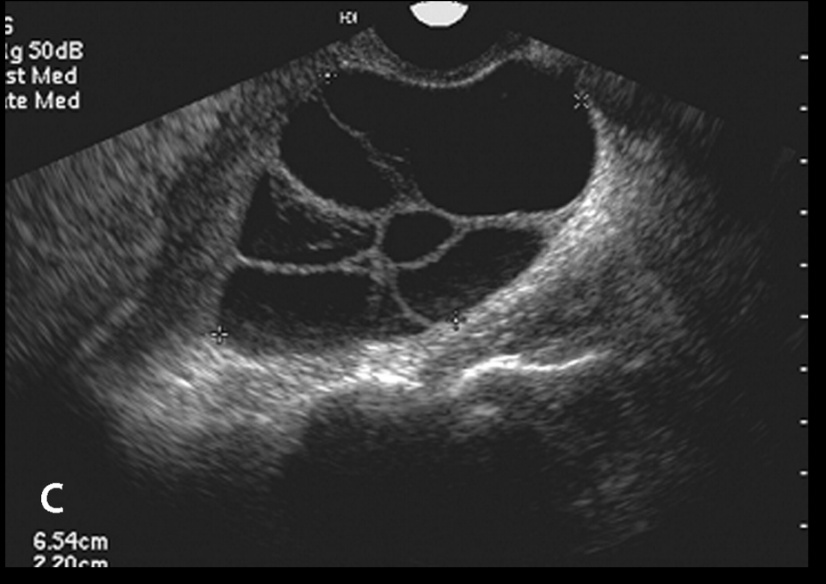

Theca-Lutein Cyst

_Theca-Lutein cysts develop from excessive gonadotropin stimulation. They will often be accompanied by abnormally high levels of beta-hCG and high levels of androgens.

Characterized by cysts lined by luteinized theca cells. Theca-Lutein cysts are often multiple and bilateral.

_Very high association with gestational trophoblastic disease, such as choriocarcinoma and hydatidiform moles.